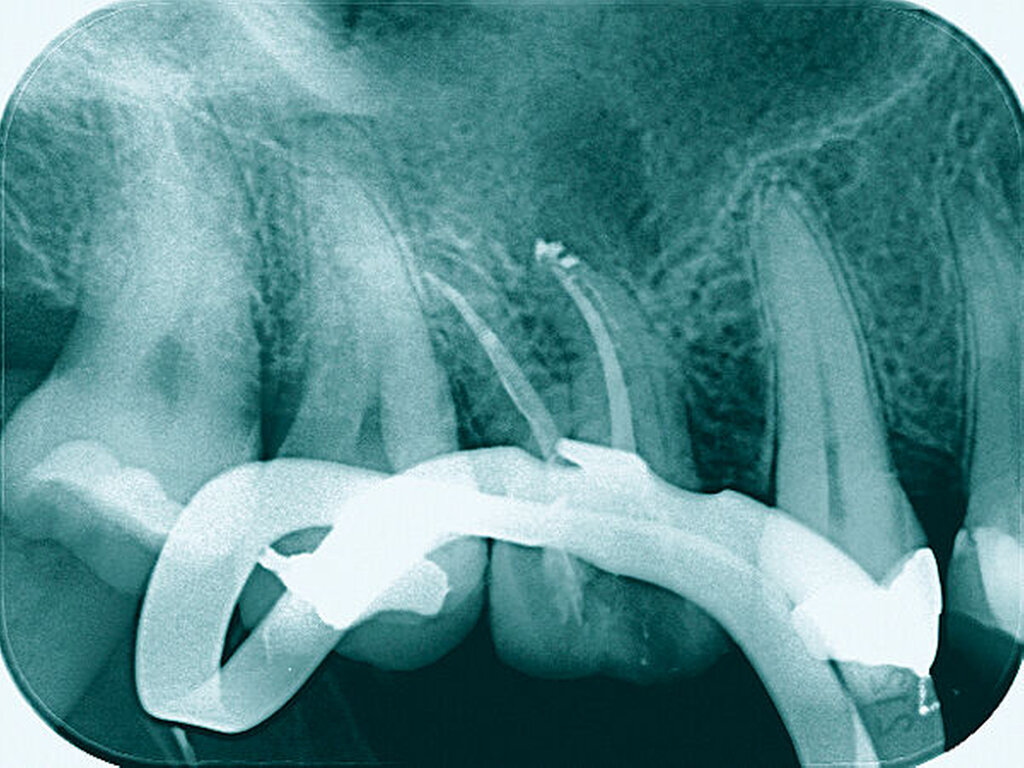

Eine 22-jährige Patientin stellte sich erstmals im Sommer 2017 mit rezidivierenden Beschwerden an dem alio loco endodontisch behandelten Zahn 16 vor. Nach ausgiebiger Aufklärung über die Therapieoptionen bei Verdacht auf einen unbehandelten mb2 erfolgte die Revisionsbehandlung des Zahnes mit der Empfehlung, diesen aufgrund des großen Substanzdefekts zur Stabilisierung zeitnah zu überkronen. Bevor die Überkronung durchgeführt werden konnte, frakturierte der palatinale Höcker. Bei der Inspektion unter dem Operationsmikroskop war sichtbar, dass sich die Fraktur als Längsfraktur in die palatinale Wurzel fortsetzte. Mit der Patientin wurden nun die Optionen der Teilamputation der frakturierten Wurzel oder alternativ der Extraktion des Zahnes besprochen. Sie entschied sich für den Erhaltungsversuch.

Darauf erfolgte die Amputation der palatinalen Wurzel mit anschließender Versorgung durch eine vollkeramische Krone. Die Situation ist nach inzwischen drei Jahren weiterhin stabil, die Patientin kommt mit der Versorgung gut zurecht, lediglich palatinal finden sich leicht erhöhte Sondierungstiefen.

Eine 54-jährige Patientin stellte sich 2018 in der Praxis vor, nachdem sie beim Essen ein Goldinlay an Zahn 16 verloren hatte. Sie klagte über eine Aufbissempfindlichkeit des Zahnes sowie über das Gefühl einer Lockerung. Klinisch zeigte sich eine tiefe Fraktur des Zahnes in mesiodistaler Richtung. Nach klinischer und röntgenologischer Diagnostik wurde die Patientin über die Möglichkeit der Extraktion mit anschließender prothetischer Versorgung der Lücke und den aufwendigen Erhaltungsversuch mittels endodontischer Behandlung des Zahnes samt Amputation der palatinalen Wurzel aufgeklärt. Die Patientin war sehr motiviert und entschied sich für den Erhaltungsversuch.

So erfolgte nach endodontischer Behandlung des Zahnes die Amputation der palatinalen Wurzel und die Versorgung des Zahnes mit einer Vollkrone. Die Situation an 16 ist seitdem stabil, allerdings zeigen sich auch hier palatinal erhöhte Sondierungstiefen, die röntgenologisch mit einem progredienten Knochenabbau im Bereich der Furkation zu korrelieren scheinen. Die Patientin gibt an, mit der Reinigung des Zahnes keine Probleme zu haben, möglicherweise ist diese jedoch durch die Einziehung im Bereich der Furkation vor allem palatinal erschwert. Die Patientin wurde daraufhin instruiert, wie sie die häusliche Mundhygiene in den schwer zugänglichen Bereichen intensivieren und verbessern kann.